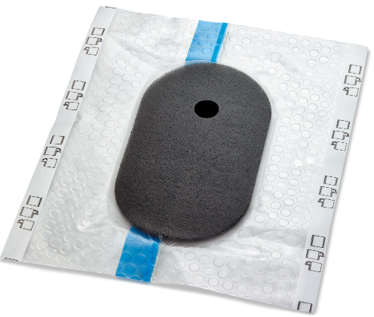

Solventum™ V.A.C.® Peel & Place Dressing

1. 3M™ V.A.C.® Granufoam Dressing

Vormt zich naar het wondbed zonder dat er vullers nodig zijn, voor een gelijkmatige negatieve druk en effectieve exsudaatverwijdering.

2. Geperforeerde niet-klevende laag

Hierdoor kan het verband worden aangebracht op de intacte huid rondom de wond, zonder eerst folie te hoeven aanbrengen. De laag is ontworpen om ingroei van weefsel tegen te gaan.

3. 3M™ V.A.C.® Dermatac™ folie

Huidvriendelijke siliconen-acryl kleeftechnologie maakt herpositioneren bij het aanbrengen mogelijk en zorgt voor een goede afdichting op vele anatomische locaties en minimaal ongemak bij het verwijderen.

4. Opening voor Solventum™ SensaT.R.A.C.™ Pad

Voorgeknipt voor eenvoudig en consistent aanbrengen van de SensaT.R.A.C. Pad.

5. Solventum™ SensaT.R.A.C.™ Pad

Helpt de druk in het wondgebied te monitoren en te handhaven.